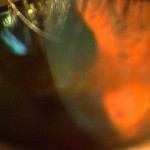

帯状角膜変性(症)は角膜の表層のボーマン膜にカルシウムが沈着して,視力低下,異物感を呈します.病因として若年性関節リウマチなどの慢性前部ぶどう膜炎,角膜の炎症,高カルシウム血症を伴う副甲状腺機能亢進症,サルコイドーシス,腎不全などがあります. 治療は視力低下がみられる場合はEDTA溶液を用いた外科的除去,エキシマレーザーによる切除があります.当院ではEDTA溶液を用いた外科的除去を行っています.下の写真は当院でのEDTAを用いた外科的除去の術前術後です.

症例1